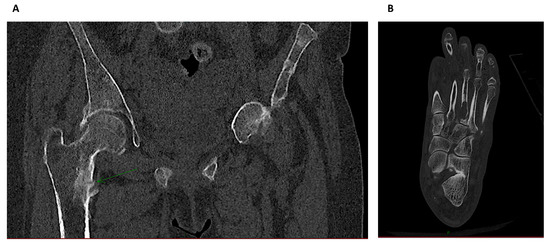

3.5. Quantitative Computerized Tomography